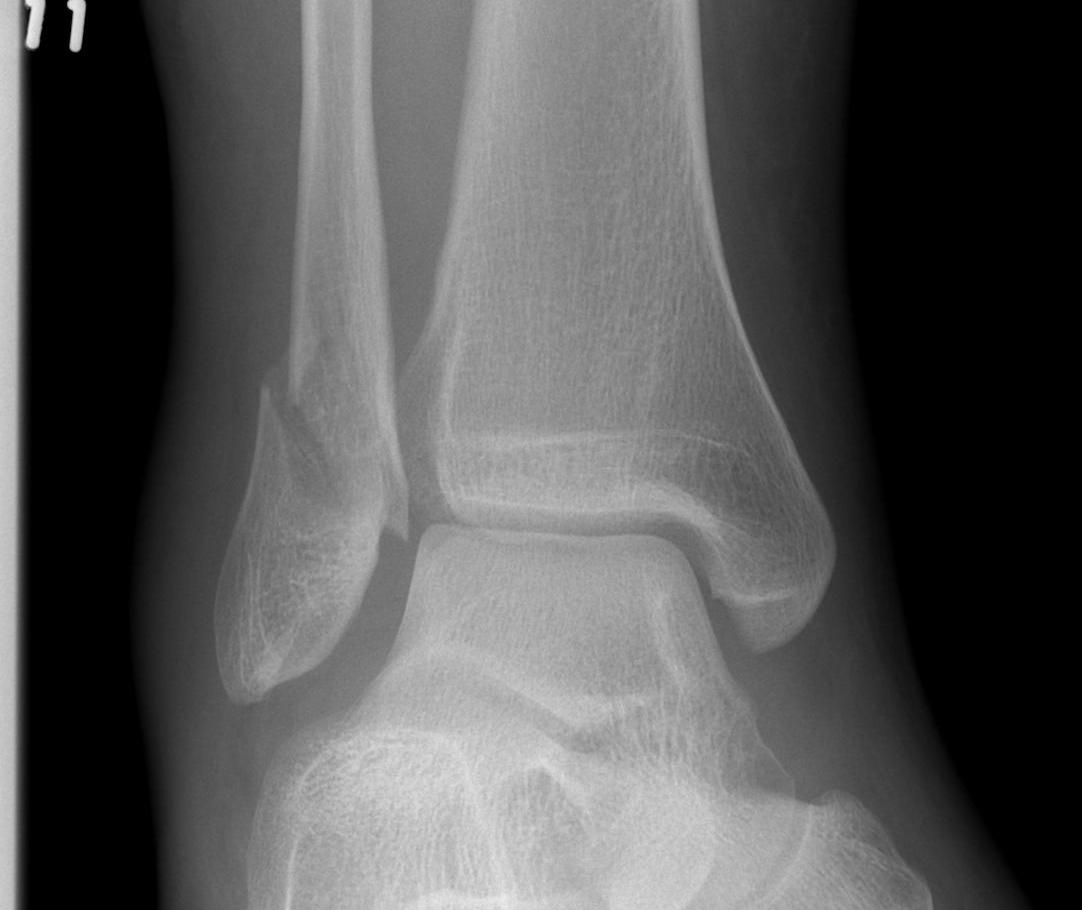

X-ray assessment

3 standard views

AP / Lateral / Mortise

Mortise

- AP with foot internally rotated

- should be symmetrical space around talus

| Increased tibio-fibular clear space | Overlap | Increased medial clear space |

Medial border of the fibula Lateral border of the posterior tibia (incisura fibularis) Measured 1 cm above the plafond |

Overlap of the fibula and the anterior tibial tubercle

Medial talus to lateral medial malleolus |

| <5mm AP and mortise |

> 6 mm AP view > 1 mm mortise view |

< 4mm Equal to superior clear space |

| Syndesmotic injury | Syndesmotic injury |

Deltoid ligament injury Lateral talar shift |